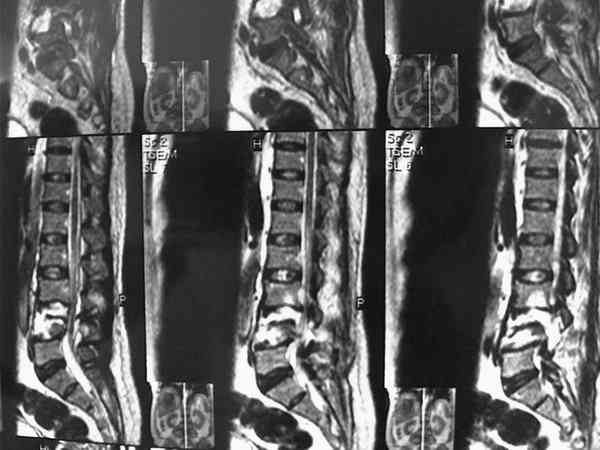

Женщина получила травму более 1 мес назад, когда оказалась под колесами крытого пикапа (мы его раньше называли "пирожковозом"). Причем машина сдавала назад, ехала не быстро и упав, женщина оказалась под тяжестью кузова и заднего моста машины. Так она пролежала, пока водитель не обнаружил ее там, а затем не позвал на помощь людей, которые машину приподымали...

При этой картине удивительно еще то, что у нее нет никаких двигательных и тазовых нарушей.. Жалобы только на боли в спине. Движения и чувствительность в полном объеме. Никаких повреждений сосудистых магистралей также нет. Только изолированный перелом L5 со смещением тела позвонка в мягих тканях (забрюшинном пространстве). Остистый отросток на месте.

В приложении - МРТ.